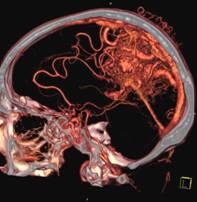

头颅一站式检查:320排容积CT覆盖范围达16cm,球管旋转一周可以覆盖整个脑组织,获得全脑0.5mm层厚各向同性全脑信息。一次扫描可以获得平扫容积图像、以时间为序列全脑动态3D-CTA图像(包括纯动、静脉期成像)及全脑灌注图像。一次检查即可排除脑出血、动脉瘤、动脉狭窄、梗塞、脑实质供血异常等多种病变及进行脑卒中筛查。

全 脑 灌 注

脑血管畸形CTA ,大血管成像:动态容积成像实现大范围动态血管检查